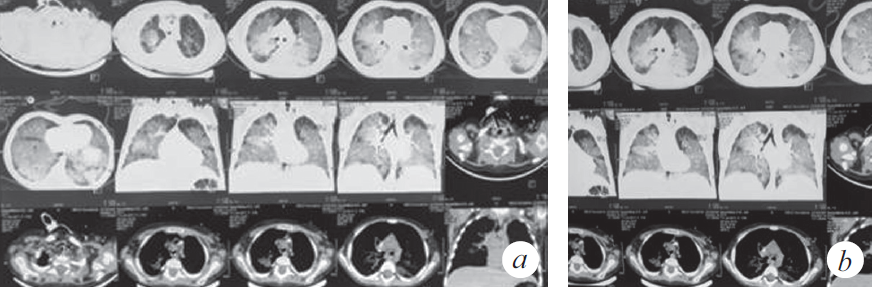

Из анамнеза заболевания известно, что 01.11.2018 ребенок по неосторожности родителей принял внутрь парафиновое масло. Мама стимулировала рвоту, после чего ребенок стал подкашливать. Бригадой скорой медицинской помощи девочка доставлена в стационар по месту жительства с диагнозом: «Острая респираторная вирусная инфекция, ларинготрахеит». О факте случайного приема парафинового масла и стимуляции рвоты мать не сообщила. Первые три дня пациентка находилась в стационаре (детская клиническая больница № 1) и, учитывая улучшение, была выписана под наблюдение участкового врача. На одиннадцатый день заболевания девочка с симптомами внебольничной двусторонней пневмонии была госпитализирована в стационар центральной клинической больницы СО РАН, с дальнейшим переводом в инфекционную больницу. По результатам компьютерной томографии (КТ) органов грудной клетки констатированы признаки диффузного интерстициального заболевания легких (рис. 1). На этом основании заподозрено аспирационное поражение паренхимы легких, вероятность которого подтвердила мать при дополнительном сборе анамнеза.

Рис. 1. Компьютерная томограмма органов грудной клетки (через 3 нед. от дебюта заболевания) (a). Признаки диффузного интерстициального заболевания легких, вероятно, двусторонняя липоидная пневмония, дифференциальный диагноз с альвеолярным протеинозом (b)

Fig. 1. CT scan of the chest (3 weeks after the onset of the disease) (a). Signs of diffuse interstitial lung disease, probably bilateral lipoid pneumonia, differential diagnosis with alveolar proteinosis (b)